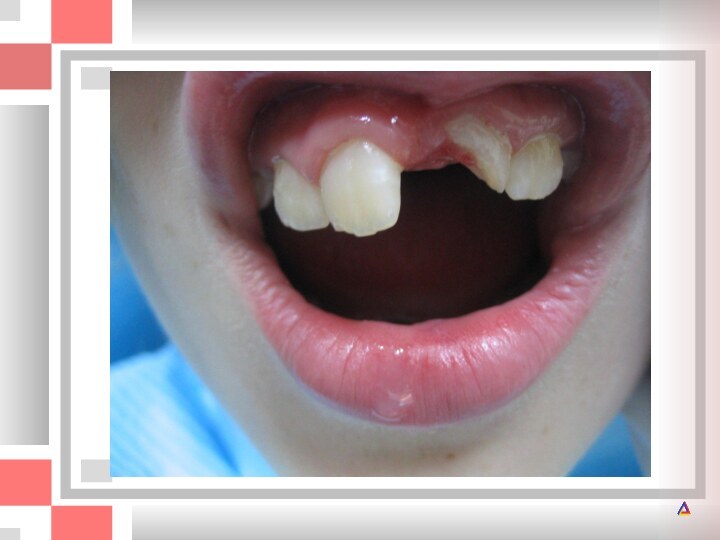

Год назад левый молочный центральный резец получил травму. После травмы зуб

После травмы зуб казался здоровым, однако впоследствии анкилозировался, что

не позволило ему полностью прорезаться.

Анкилоз постоянного центрального резца после травмы. Прорезывание резца прекратилось. Зуб следует удалить.